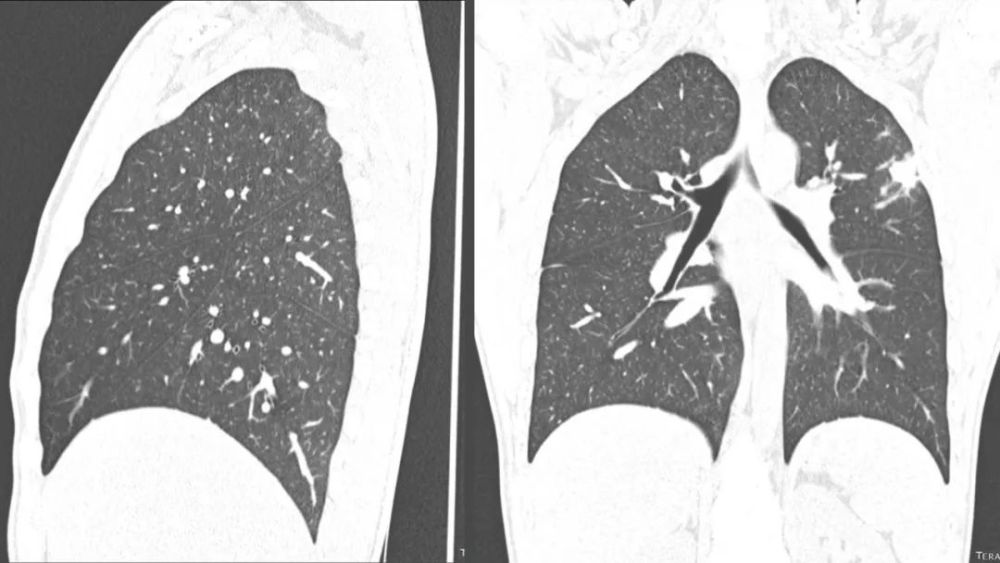

上副裂/叶

Superior accessory fissure

右肺下叶的上副叶 , 位于水平裂后方 , 将右肺下叶分为 上和基底段 , 称为后叶或背叶( posterior or dorsallobe)

可以完整或不完整 右肺多